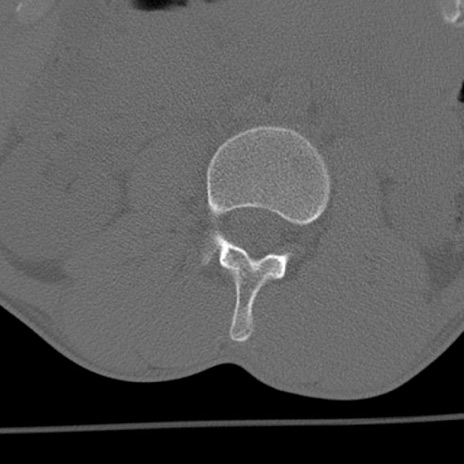

症例3 腰椎CT(横断像)

腰椎CT